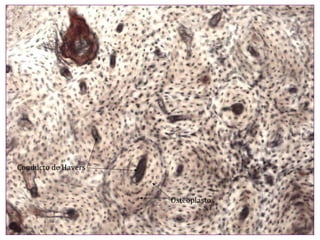

El documento describe diferentes aspectos de la histología del cartílago y el hueso, incluyendo las estructuras del cartílago como condroblastos, matriz y lagunas, y las estructuras óseas como conductos de Havers, osteoblastos y osteoclastos. También describe las etapas de la osificación endocondral, el proceso por el cual el cartílago se transforma en hueso, incluyendo las zonas de cartílago en reposo, proliferación, hipertrofia, erosión y osificación.